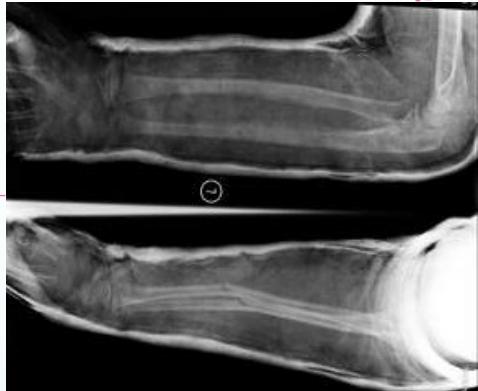

Stable Fractures - Incomplete

- Greenstick

- Buckle (Torus)

- Plastic deformation